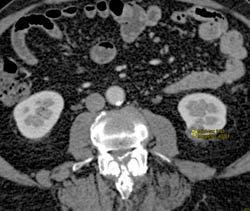

Complex Right Renal Cyst With Calcification